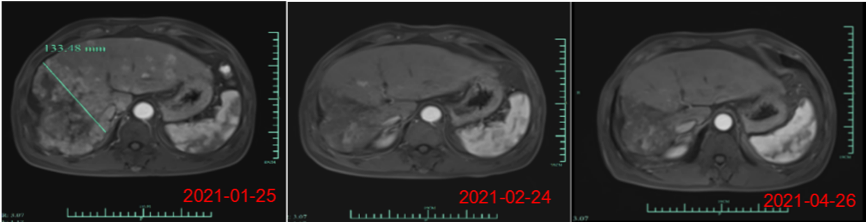

楊煥鳳表示,近期公司在美國(guó)臨床腫瘤學(xué)會(huì) (ASCO)發(fā)表了核心產(chǎn)品Ori-CAR-001在治療難治復(fù)發(fā)型肝細(xì)胞癌的探索性臨床研究數(shù)據(jù),截至三月份,在9例可評(píng)估數(shù)據(jù)中,有4例獲得PR(部分緩解),截止到目前,受試者007的緩解周期已超過是9個(gè)月,還有一例受試者012的PR緩解周期已達(dá)5個(gè)月,其腫瘤縮減的幅度接近93%。

此外,最近的一個(gè)新的爬坡劑量的首個(gè)患者也獲得了PR(自ASCO數(shù)據(jù)發(fā)布后,又新增了一位部分緩解的病人)。目前,這些病患目前仍在持續(xù)隨訪中。“在晚期實(shí)體腫瘤治療中,這個(gè)緩解時(shí)間還是相當(dāng)長(zhǎng)的,腫瘤減小的幅度也是非常驚人的,這個(gè)結(jié)果令團(tuán)隊(duì)很受鼓舞,我們期待在進(jìn)一步的產(chǎn)品開發(fā)和臨床研究過程中,獲得更好的數(shù)據(jù)。